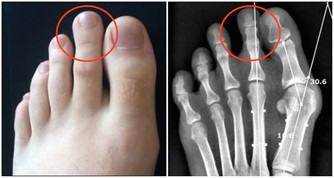

關節軟骨大概有1到2毫米,作用就是緩沖壓力,保護骨骼不破裂。

它就相當於跑道上的橡膠,能夠幫助大家緩衝上下運動時的一個力,進而來保護自己的關節。

在堅硬地板上運動,在超強的反作用力下彈回來,對關節和骨骼的損傷相當大。因此,建議多在橡膠運動場地做運動。